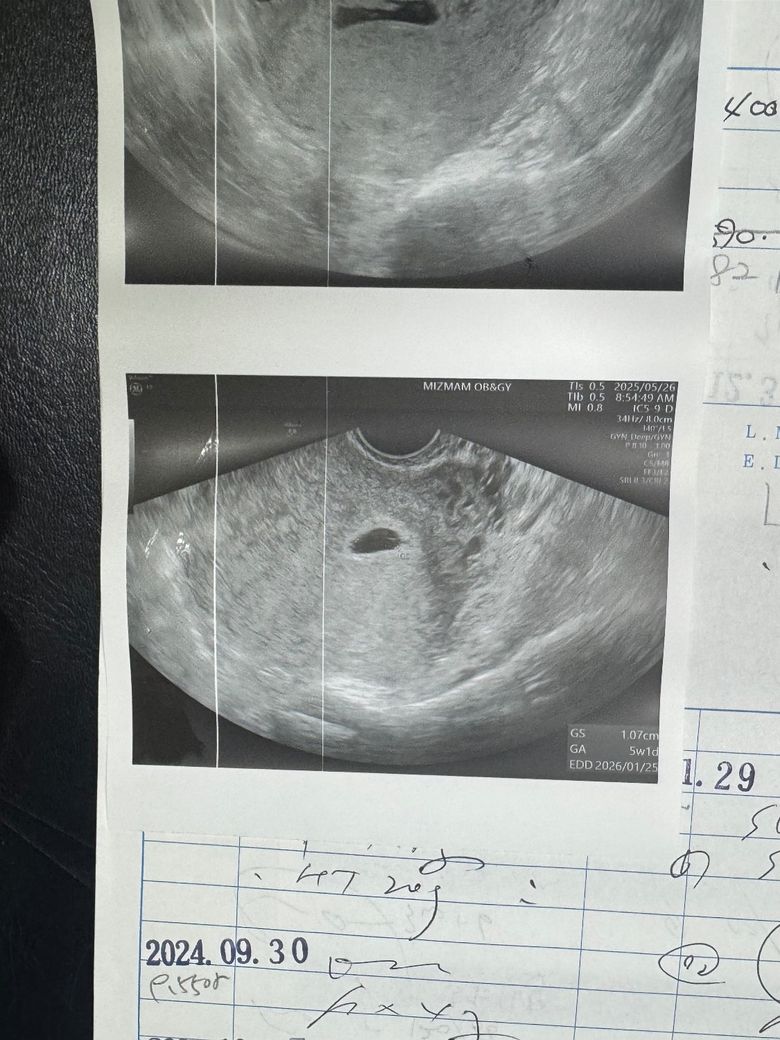

임신 5주1일 초음파 있고 난황 없어요

모양이 이상하고요 난황도 안보이고해요 ㅠㅠ

선생님 이가 이거 인심인지 아닌지 아직 말이 어렵대요 이거 정상 맞나요? 도와주세요 ㅠ

• 아직 너무 초기에 해당하기 때문에 명확하게 이야기를 해주시지 못하고 있는 것일 수도 있습니다. 사진으로 올리신 것만 놓고 무어라 이야기를 하기에는 애매합니다. 한 번 초음파 보고 끝날 것은 아니기 때문에 다음 진료 때 한 번 더 제대로 파악이 될 수 있기를 기다려보시는 것이 적절할 것으로 사료됩니다.